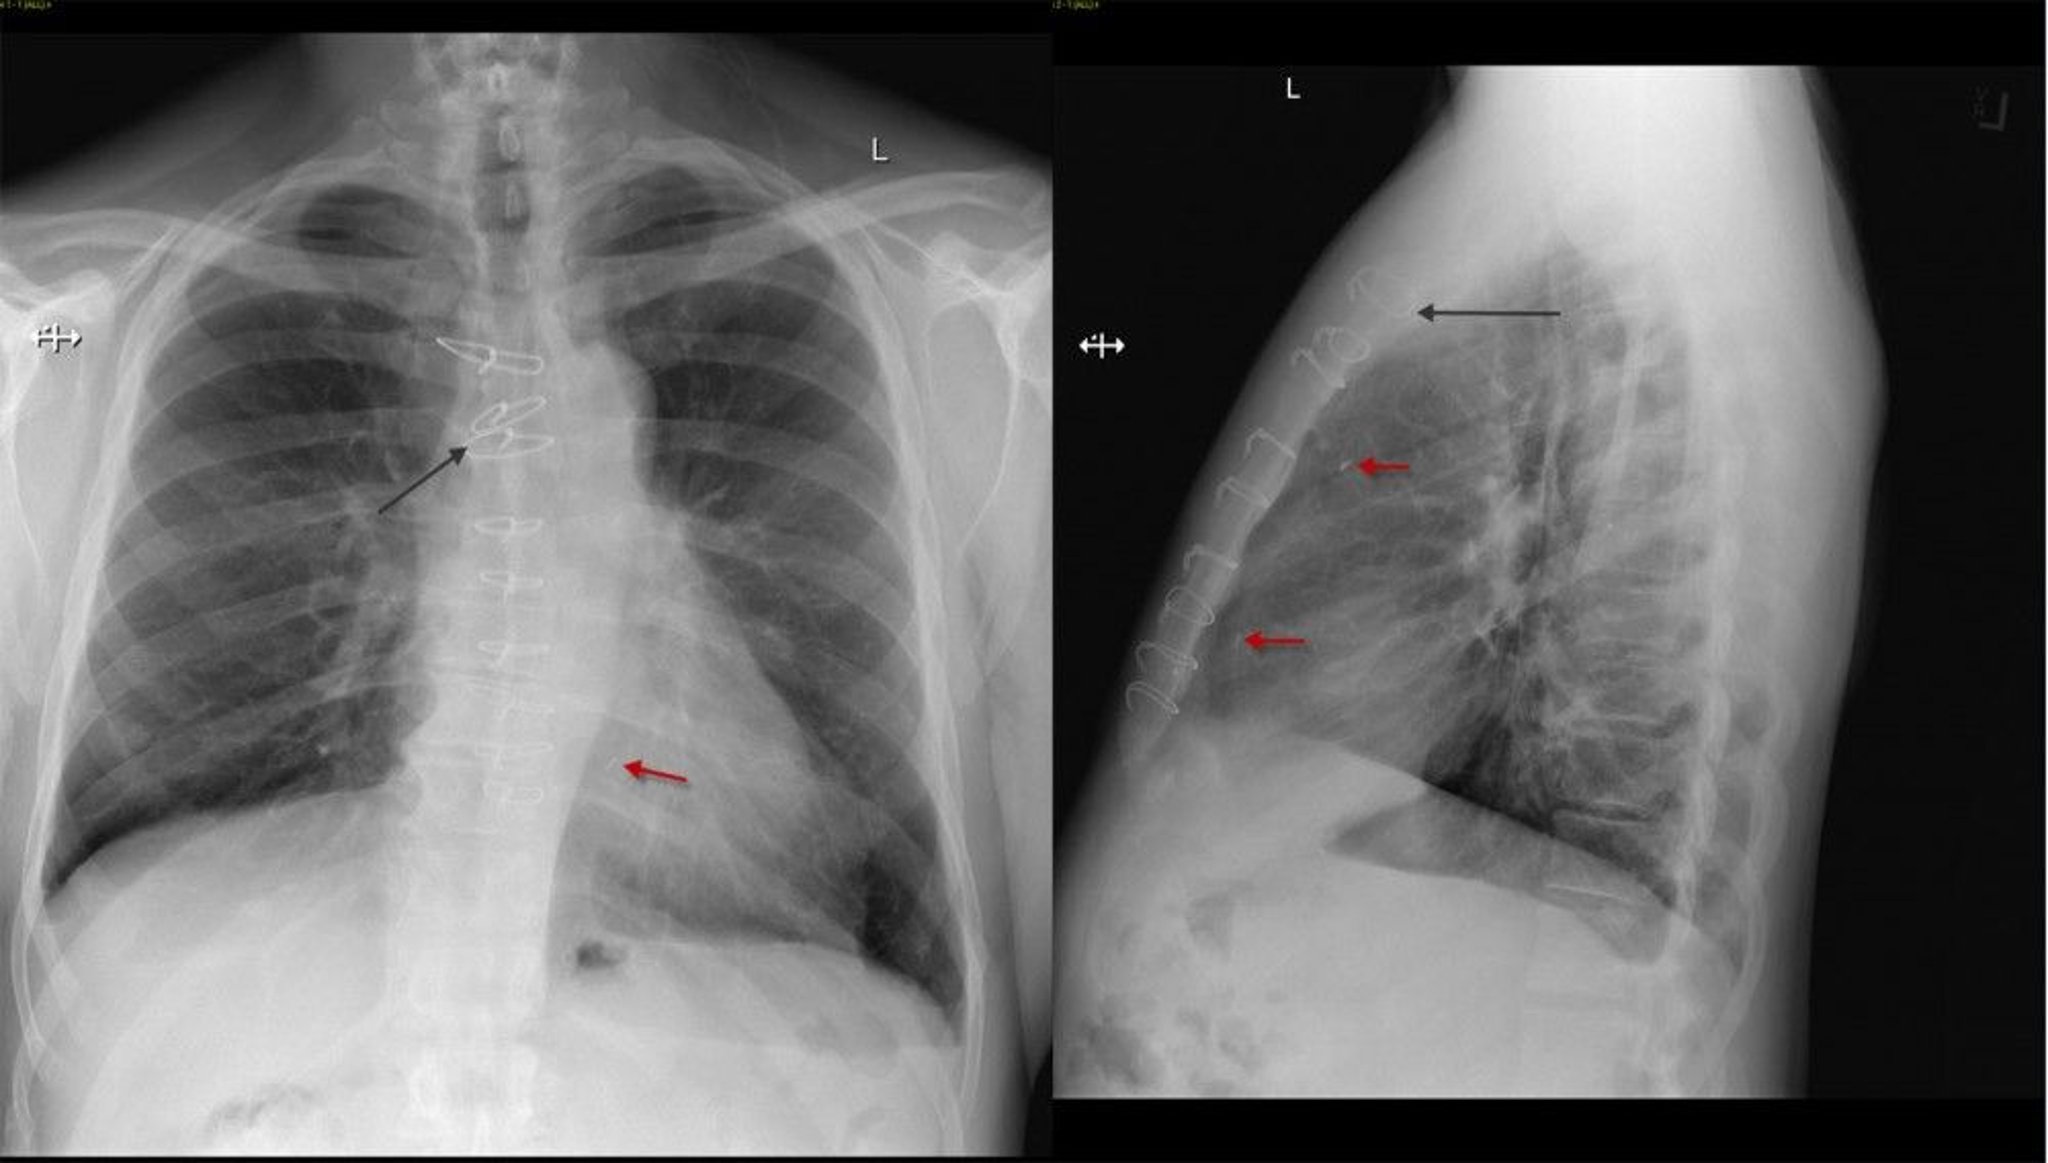

Chest X-Ray of a Patient After Coronary Artery Bypass Surgery

Frontal and lateral chest x-ray of a patient post coronary artery bypass surgery showing sternal sutures (black arrow) and surgical clips (red arrow).